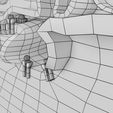

神经肌肉接头示意图